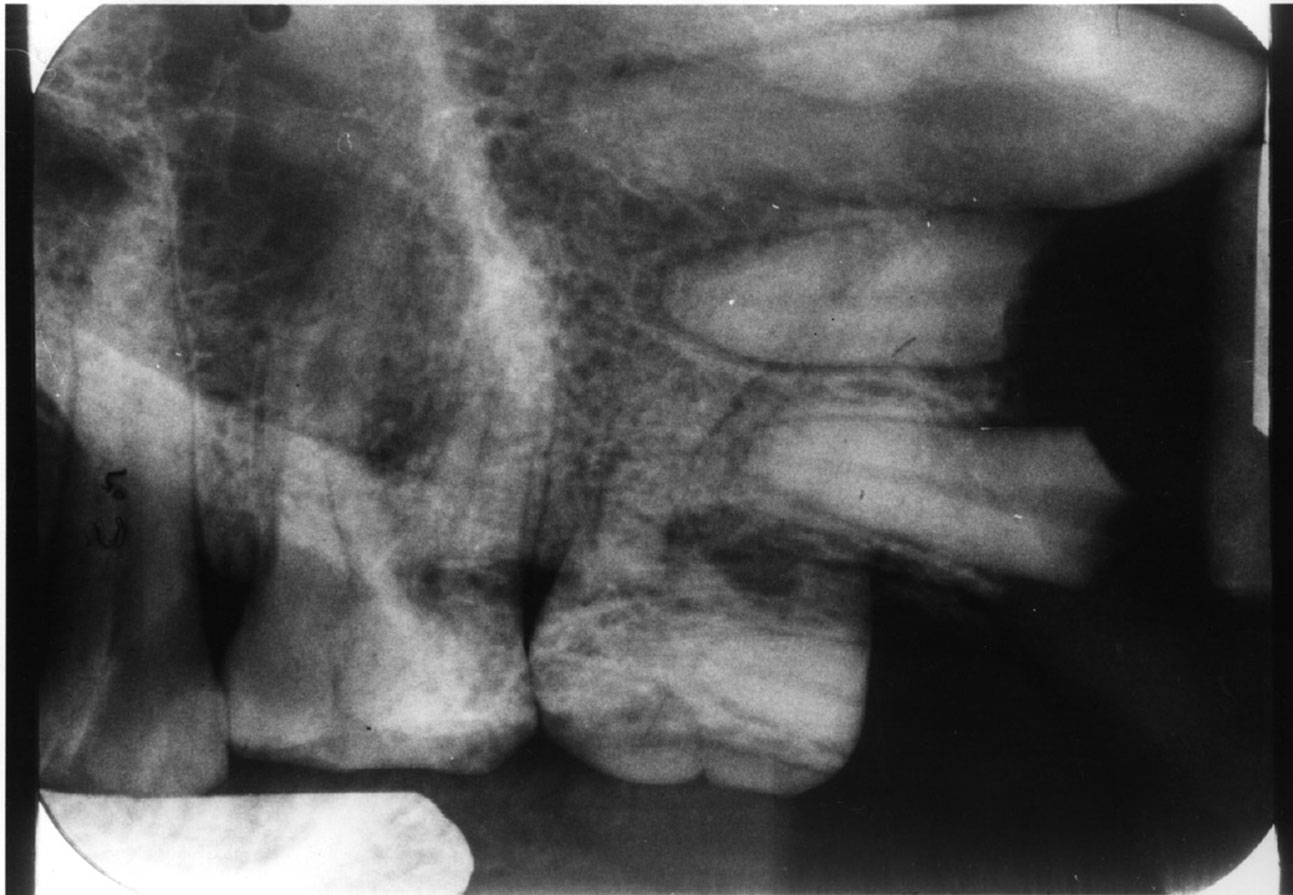

Film Placement

6. Vertical-Horizontal film placement errors: It is possible to misalign the film so that it is incorrect on both positions, compounding the effects of the individual positioning errors. Figure 7 is a radiograph which resulted from the film being positioned too far posteriorly in the horizontal position and too high in the vertical position. Notice that due to these placement errors, the mesial surface of the first mandibular premolar and the apices of the first and second mandibular premolars are not recorded.

Remedy: The operator must place the XCP bite block directly on the teeth being radiographed. The patient must bite hard enough to hold the XCP bite block in place. If the patient finds that the bite block and the film are uncomfortable, the operator must reposition the film, possibly tilting the film or using a different holder, however the operator must maintain the correct placement.

Figure 7. Vertical horizontal film placement error.

Figure 7